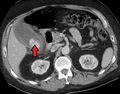

![]() Acute cholecystitis as seen on CT. Note the fat stranding around the enlarged gallbladder. | |